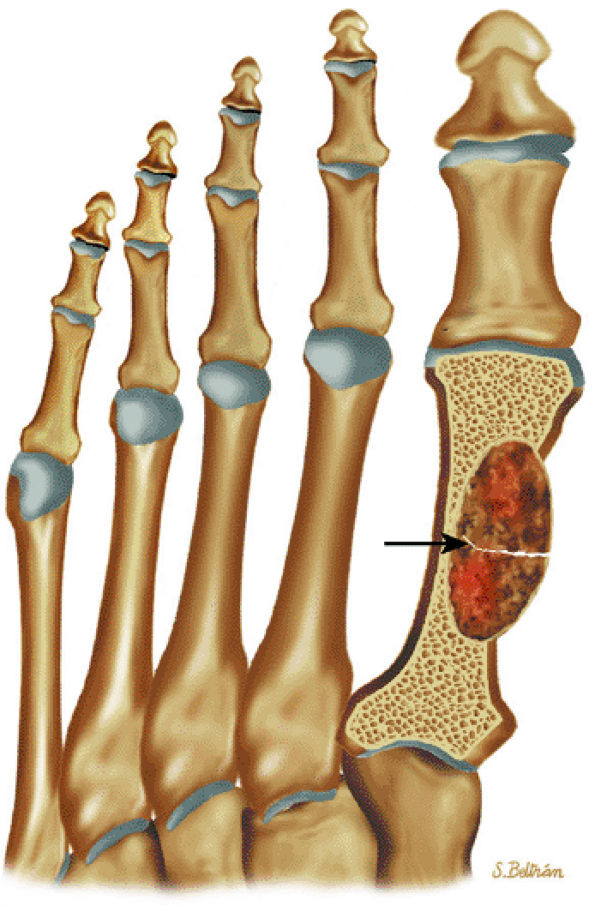

FIGURE 14-89 ● Metastatic lung cancer to the foot. Coronal graphic illustration shows a metastatic lesion with a pathologic fracture (arrow) involving the metatarsal. Metastases to the hands and feet are usually from lung cancer.